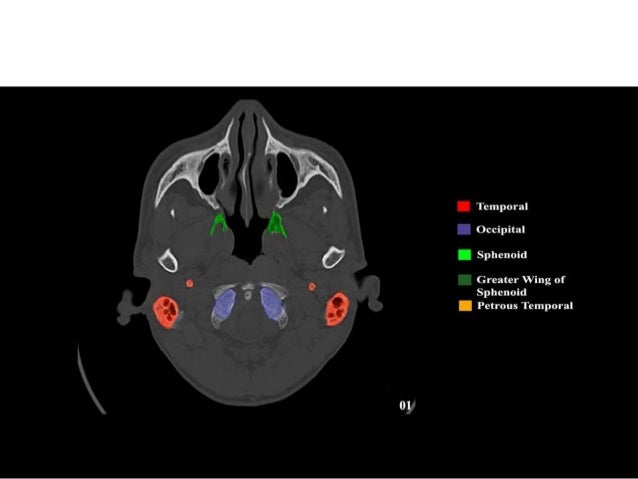

39+ Skull Base Anatomy Ct Scan. These pictures of this page are about:bone skull base anatomy ct. Learn about the anatomy of the skull bones and sutures as seen on ct images of the brain.

Medical Imaging And Radiological Anatomy X Ray Ct Mri Kenhub from thumbor.kenhub.com Axial ct bone window of skull base from inferior to superior aspect. This article will describe the anatomical structures which can be seen from a superior view of the skull base. This anatomic region is complex and poses surgical anatomy of the skull base, temporal bone, external ear, and middle ear.

Dural venous sinuses, veins, arteries. The patient drank positive oral contrast agent (the contrast is in the small intestines). Images are shown from the vertex to the base of the skull. The floor of the cranial cavity, on which the brain rests.